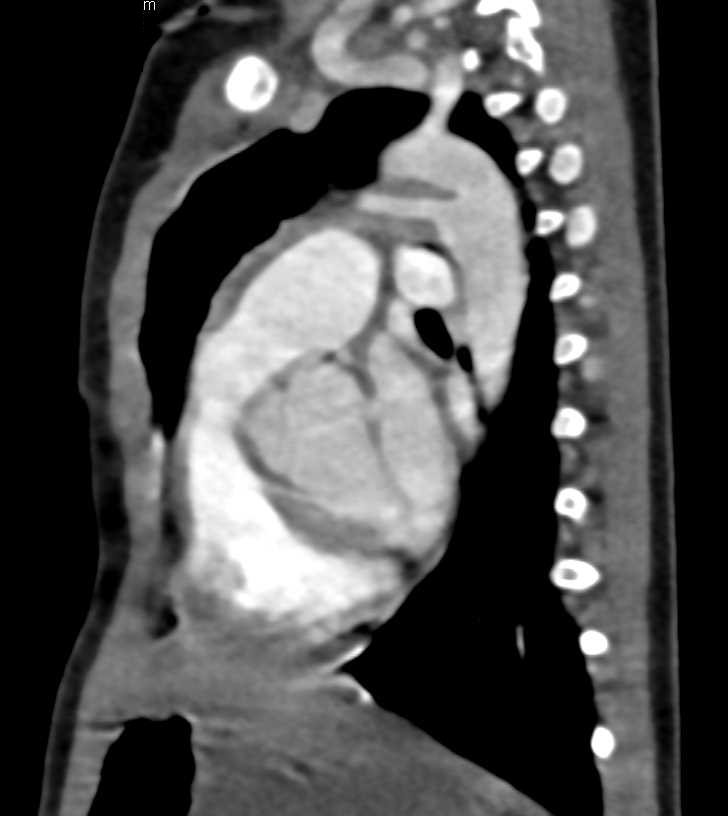

Small Right Pneumothorax Post Biopsy